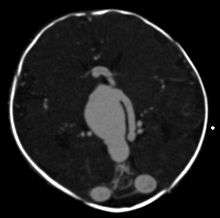

An AVM diagnosis is established by neuroimaging studies after a complete neurological and physical examination.[3][4] Three main techniques are used to visualize the brain and search for AVM: computed tomography (CT), magnetic resonance imaging (MRI), and cerebral angiography.[4] A CT scan of the head is usually performed first when the subject is symptomatic. It can suggest the approximate site of the bleed.[1] MRI is more sensitive than CT in the diagnosis of AVMs and provides better information about the exact location of the malformation.[4] More detailed pictures of the tangle of blood vessels that compose an AVM can be obtained by using radioactive agents injected into the blood stream. If a CT is used in conjunctiangiogram, this is called a computerized tomography angiogram; while, if MRI is used it is called magnetic resonance angiogram.[1][4] The best images of an AVM are obtained through cerebral angiography. This procedure involves using a catheter, threaded through an artery up to the head, to deliver a contrast agent into the AVM. As the contrast agent flows through the AVM structure, a sequence of X-ray images are obtained.[4]